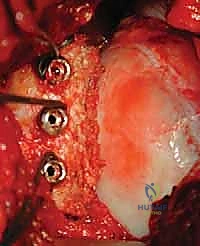

الخطوة 3: تحضير موقع الاستقبال (التجويف الحقاني)

يتم تنظيف الحافة الأمامية للتجويف الحقاني من الأنسجة الندبية والغضاريف التالفة. يستخدم الدكتور هطيف أدوات دقيقة لكشط سطح العظم حتى يصل إلى عظم ينزف (Bleeding bone)، وهو أمر بالغ الأهمية لضمان اندماج الطعم العظمي الجديد.

الشكل 9 • تحديد وتحضير السطح العظمي في التجويف الحقاني الذي سيستقبل الطعم العظمي الجديد.

الخطوة 4: حصاد الطعم العظمي من الحوض (Bone Graft Harvest)

من خلال شق صغير في منطقة الحوض (Iliac Crest)، يتم استخراج قطعة عظمية (Tricortical graft) بالحجم الذي تم التخطيط له مسبقاً في الأشعة المقطعية. يتم إغلاق جرح الحوض بعناية فائقة لتقليل الألم بعد العملية.

الشكل 10 • عملية أخذ الطعم العظمي الذاتي من عظم الحرقفة (الحوض)، وهي منطقة غنية بالعظم الإسفنجي والصلب.